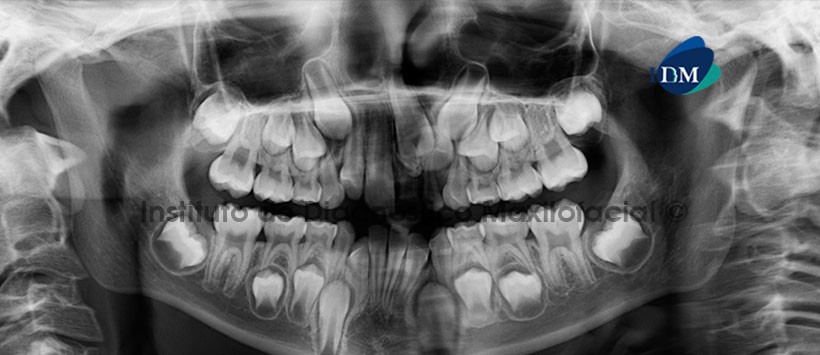

A la evaluación de la radiografía panorámica (Figura 1), observamos la presencia de una imagen radiopaca de densidad dentaria localizada en el reborde alveolar correspondiente a las piezas 2.1 y 2.1, condicionando la impactación de dichas piezas